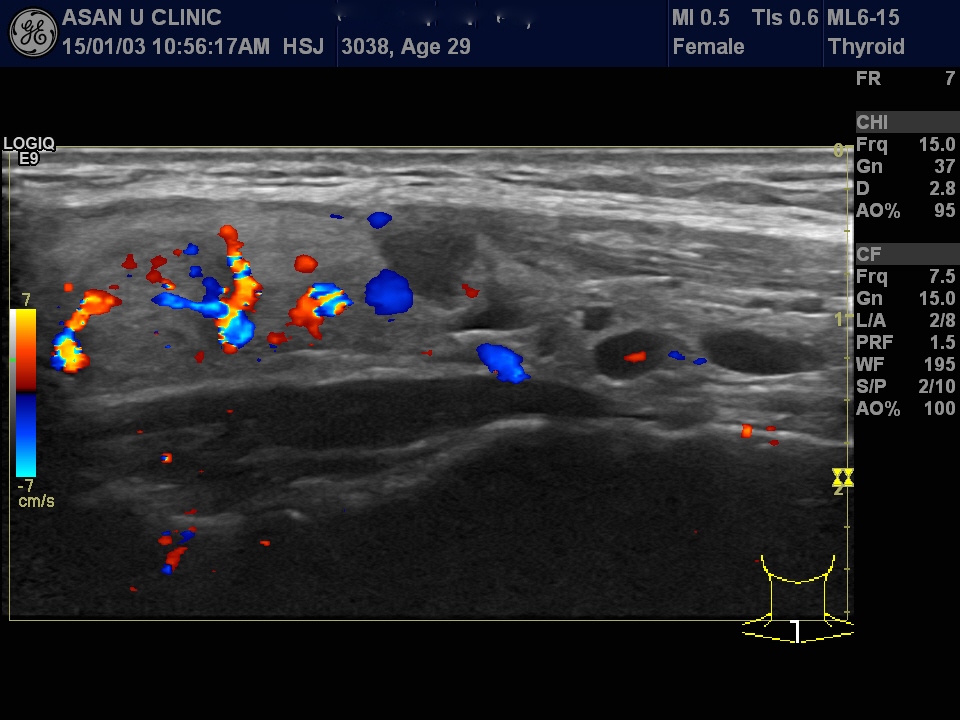

목이 볼록하다고 내원한 29세 여성입니다.

갑상선 초음파상 양측 갑상선 위아래로 여러개의 다양한 크기의 혹들이 있었으며

그 중 가장 의심스러운 혹을  세침흡인검사를 실시하여

갑상선의 유두암세포를 확인하였습니다.